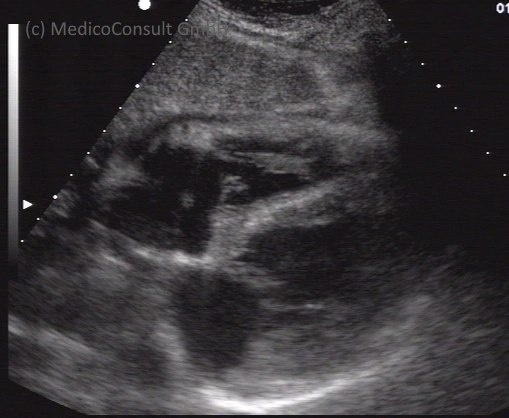

Die Echokardiographie (Kurzbezeichnung: Herzecho) ist eine bildgebende Untersuchungsmethode zur Diagnostik von Herzerkrankheiten. Sie ermöglicht Aussagen zur Struktur und Form des Herzens, seiner Muskulatur und Klappen, sowie zu seiner Funktion. Weil sie bei transthorakaler Anwendung (von außen) rasch durchzuführen, nicht patientenbelastend und außerordentlich aussagekräftig ist, wird sie inzwischen in der Kardiologie routinemäßig angewendet.

Eine transösophageale Echokardiographie (TEE, „Schluckecho“) lässt eine genauere Aussage zu und wird vor allem zur Diagnostik der Herzklappen und von offenen Foramina in den Herzwänden angewendet. Bei ihr sitzt der Schallapplikator an der Spitze eines Endoskops, welches geschluckt werden muss. Diese Methode ermöglicht auch eine genauere Untersuchung der herznahen Blutgefäße. 1

Die Stressechokardiographie kombiniert die Methode der transthorakalen Echokardiographie mit einer erhöhten Herzbelastung, die durch Muskelarbeit an einem Ergometer oder medikamentös durch Anregung des Sympathikus (durch ein Sympathicomimekikum) erzeugt wird. Sie ermöglicht den Nachweis einer kritischen Unterversorgung eines Muskelbezirks mit Blut, die erst unter Belastung zutage tritt. Diese Methode ist eine Routineuntersuchung zur Diagnostik einer koronaren Herzkrankheit geworden. 2

Die Kontrastmittel-Echokardiographie ermöglicht den Nachweis selbst minimaler Blutflüsse. Es werden Mikrobläschen intravenös injiziert, die im Herzen eine Reflexsteigerung bewirken. Im Fall pathologischer Blutflüsse, z. B. eines Septumdefekts, oder einer intrakardialen Raumforderung (z. B. durch einen Thrombus oder ein Myxom) kann sie die Aussagekraft erheblich steigern. 3